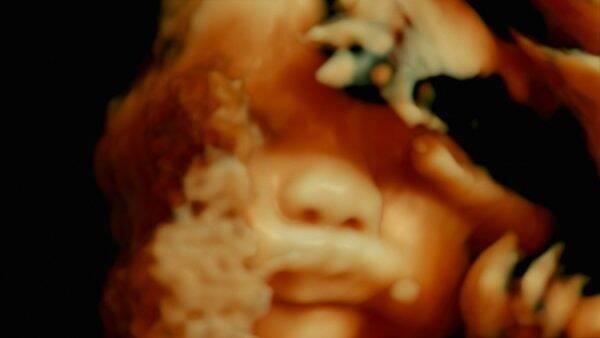

Encore une fois, c’est du documentaire qu’est venue l’incarnation, soit ce moment rare où le réel, la chair et la matière s’incorporent dans un dispositif cinématographique, lui conférant la force, la beauté, mais aussi l’antique cruauté du vivant. Venus de l’anthropologie, Véréna Paravel et Lucien Castaing-Taylor prolongent avec De humani corporis fabrica le traité d’anatomie éponyme d’André Visale et exposent donc la fabrique, la machinerie, la tuyauterie du corps humain, déployant l’imagerie exploratoire de la médecine moderne – opération à crâne ouvert, endoscopies, chirurgie oculaire ou accouchement par césarienne – selon les lois de la perspective expérimentale, procédant par là même au retour de la corporalité, jusqu’alors relégué dans les ténèbres, dans le domaine du visible. L’horizon soudainement ouvert au regard du spectateur, la science-fiction n’aurait pas pu l’inventer, incapable de réunir sous un même régime plastique l’exactitude de l’enregistrement scientifique et le foisonnement d’abstractions délirantes, l’engendrement du monde biologique et son extension permanente à une dimension cosmique. Quel plan pourrait mieux raconter le vertige des échelles que ce gros plan d’un œil sanguinolent, semblable à une naine rouge au bord de l’effondrement ? Comment mieux rendre compte de la violence de l’arrachement au paradis amniotique qu’en filmant ces mains qui écartèlent le ventre maternel ? Et que dire de ces pinces de métal qui serpentent à travers les tissus, manipulent et ablatent les organes, comme animées de leur volonté propre, sinon que leur puissance d’évocation ouvre une fenêtre terrifiante sur les lendemains post-humains ?